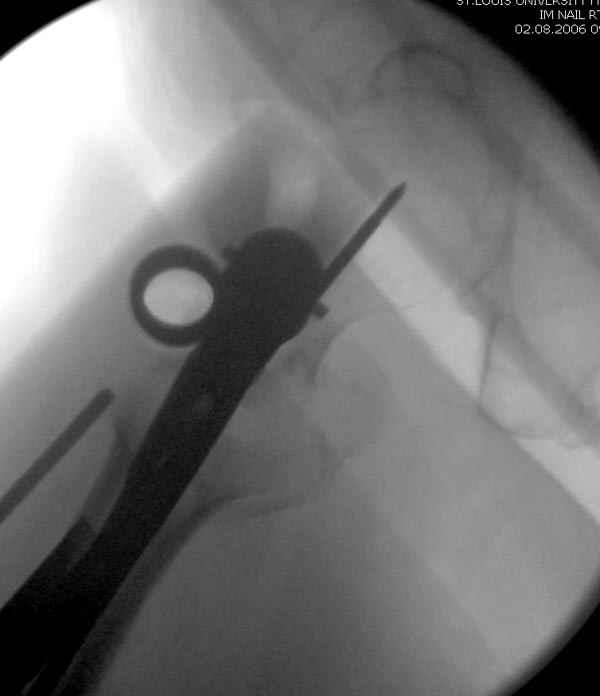

Мы получили испытательный вариант инструментария для пробы, хотя компания объявила, но ещё не для широкой публики, обещают к сентябрю. За полтора месяца, включая сегодняшнюю, вот уже восьмая операция по счету. Удобный инструментарий, ничего лишнего, научились делать быстро, посмотрим что будет, пока нравится.

Здесь сканнированные снимки импланта и операционные снимки больной.

На этом снимке процесс компрессии нижним болтом.

Итог

Александр, поздравляю от души, отличная работа, вообще-то и у меня тоже были опасения по поводу латеральной стенки. Идеальное показаниt к применению импланта закрытым методом при таких переломах, когда болт замыкается в штифте, конструкции придается угловая жесткость, примерно как в Blade Plate.

В течении последних двух лет на рынке появились множество других трохантерных штифтов, включая TTFN helical screw Synthes, вот недавно Smith Nephew Richards заимел новый имплант, азработанный Roy Sanders.